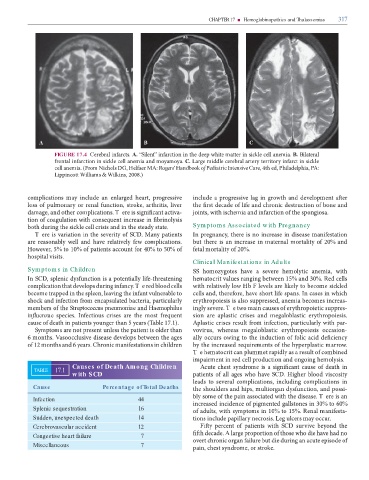

A B C

FIGURE 17.4 C . A. “S ” m k m . B. B

k m m m . C. L m k

m . (F m N DG, H MA: Rogers’ Handbook o Pediatric Intensive Care, , P , PA:

L W m & W k , .)